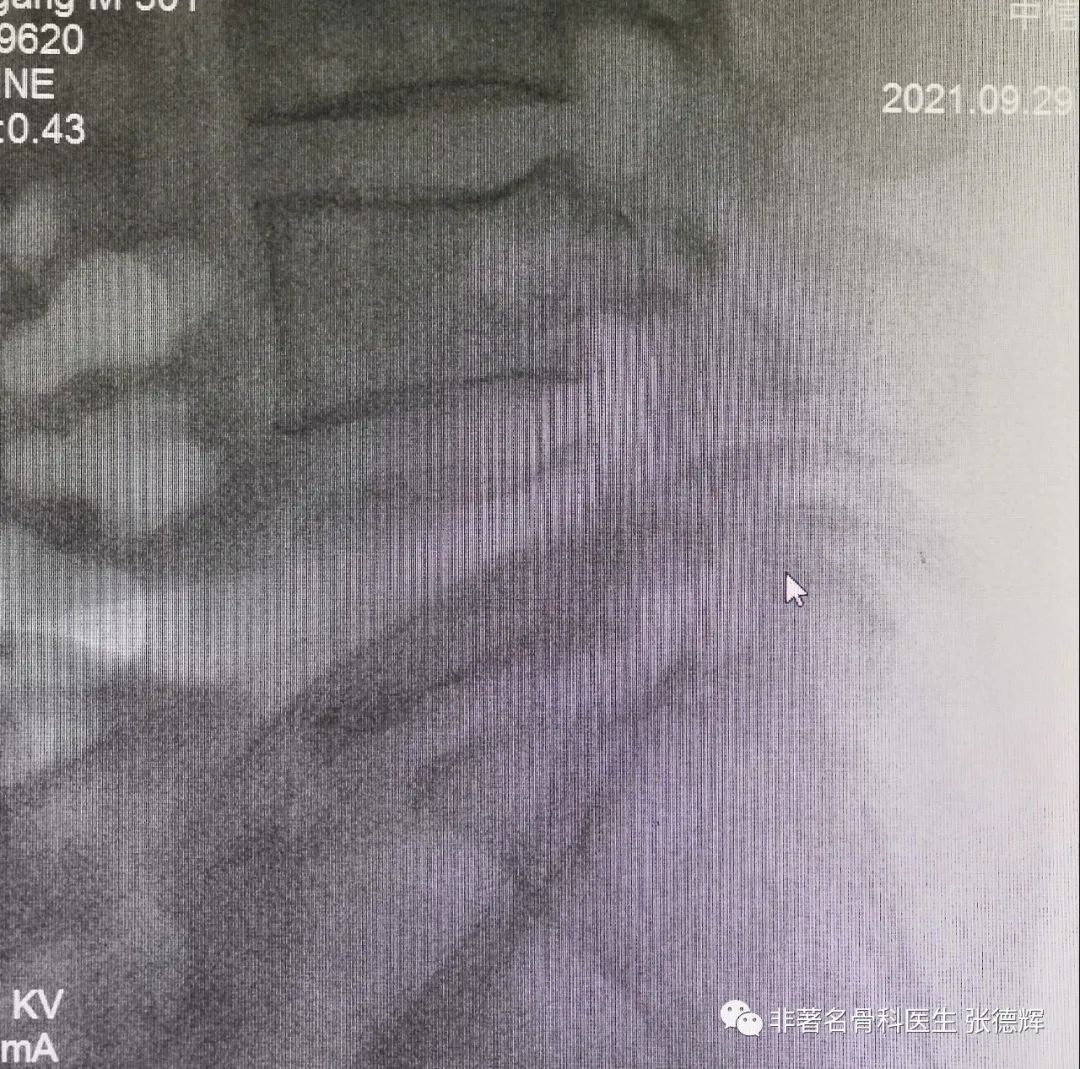

腰椎动力位片(过伸过屈位片)可见腰5相对于骶1轻度滑移

腰椎CT密扫可见腰5双侧峡部骨质结构不连续